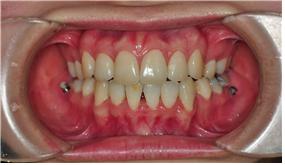

이번 교정치료는 와이어교체입니다~

와이어교체하면서 잇몸이 약하다고 말씀하시더라구요 ㅠ.ㅠ

이놈에 잇몸… 진짜 매달마다 잇몸 때문에 치료받을 때 문제가 있는 거 같아요~

선생님께서 잇몸이 약해서 당기기를 늦추고 있는 거라고 하셨습니다 ㅠ.ㅠ

그러면서 지속적으로 상악앞니를 위로 올리는 장치는 제거하지 않았구요~

곧 다음 치료에 하악앞니도 밀어넣도록 브라켓을 굵은 것으로 다시 재장착하실 거라구 하셨

어요~ㅠ.ㅠ

와이어랑 고무줄만 교체하고 진료 끝~

잇몸만 건강하다면 치료 진행이 이렇게 느리진 않을텐데,

요놈의 잇몸 때문에 요즘은 치료의 진척이 별루 없네용~

그래도 발치공간은 조금씩 닫히고 있는 거 같습니다~